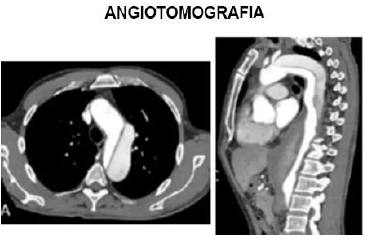

Paciente, homem, 66 anos, comparece a consulta ambulatorial assintomático. Refere ser tabagista pesado. Refere que há 3 meses teve quadro de dor torácica importante, referida como pior dor da vida com irradiação para as costas. Foi ao Pronto Socorro, sendo realizado Eletrocardiograma e marcadores de necrose miocárdica que estavam normais e então recebeu alta. No exame físico, paciente não apresenta alterações. Pela suspeita diagnóstica de etiologia da dor torácica que aconteceu há 3 meses, foi solicitado o exame abaixo e o paciente traz no retorno em 1 mês, mantendo-se assintomático:

Enunciado 1351546-1

Analise as afirmativas abaixo:

I. O paciente provavelmente apresentou dissecção aguda de aorta na sua ida ao Pronto Socorro há 3 meses. Pelo achado da imagem, pode-se concluir que se trata de Dissecção de Aorta Stanford A.

II. Nos casos de dissecção crônica (caso do paciente), deve-se avaliar outros parâmetros para indicação cirúrgica, como tamanho de aneurisma de aorta, se dor refratária, Insuficiência aórtica associada.

III. Caso na ida ao Pronto Socorro tivesse sido realizada a tomografia e identificado o diagnóstico, o paciente tinha indicação cirúrgica de urgência/emergência.

IV. Deve-se prescrever medicações para manter o controle do duplo produto, ou seja, manter Pressão arterial bem controlada e frequência cardíaca próximo a 60 batimentos por minuto.

Assinale a alternativa correta.